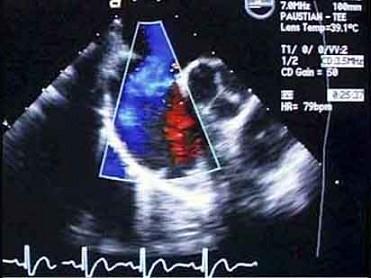

问题 女,3岁半,体检是发现胸骨下缘近心尖区可听到ⅡⅢ级收缩期杂音。经超声心动图检查,如图,确诊为房间隔缺损。杂音产生的机制是由于 ( )

选项 A、右心室流出道相对狭窄 B、二尖瓣相对狭窄 C、右心房血流量增加 D、三尖瓣相对关闭不全 E、血流通过房间隔缺损时

答案 D